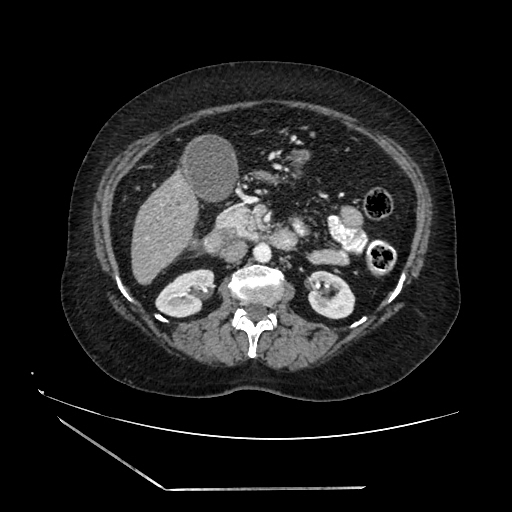

A 70 years old woman with Obstractive jaundice & palpable GB